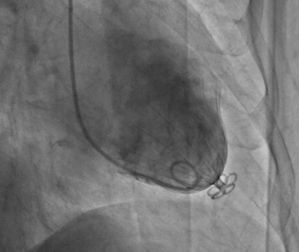

術後左室造影北京大學第一醫院心血管內科(以下簡稱“北大醫院心內科”)在科主任霍勇教授的帶領下,於2013年10月9日在國內率先通過微創介入的方法對兩名陳舊前壁心肌梗死合併室壁瘤患者施行了經皮心室重建術,

北大醫院心內科經過周密的術前準備,由霍勇教授、洪濤教授分別為兩名患者成功地將“降落傘”-左室隔離裝置放置到患者心室中,減少患者心臟的容積,有效改善心力衰竭的臨床症狀。兩名患者恢復良好。